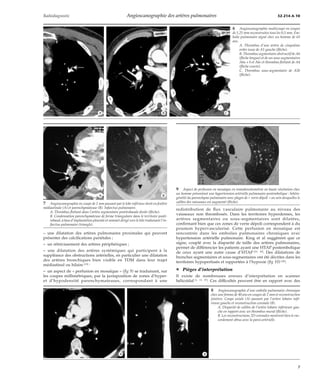

9 Aspect de perfusion en mosaïque en tomodensitométrie en haute résolution chez

un homme présentant une hypertension artérielle pulmonaire postembolique : hétéro-généité

du parenchyme pulmonaire avec plages de « verre dépoli » au sein desquelles le

calibre des vaisseaux est augmenté (flèche).

redistribution de flux vasculaire pulmonaire au niveau des

vaisseaux non thrombosés. Dans les territoires hyperdenses, les

artères segmentaires ou sous-segmentaires sont dilatées,

confirmant bien que ces zones de verre dépoli correspondent à du

poumon hypervascularisé. Cette perfusion en mosaïque est

rencontrée dans les embolies pulmonaires chroniques avec

hypertension artérielle pulmonaire. King et al suggèrent que ce

signe, couplé avec la disparité de taille des artères pulmonaires,

permet de différencier les patients ayant une HTAP postembolique

de ceux ayant une autre cause d’HTAP [21, 42]. Des dilatations de

bronches segmentaires et sous-segmentaires ont été décrites dans les

territoires hypoperfusés et rapportées à l’hypoxie (fig 10) [40].